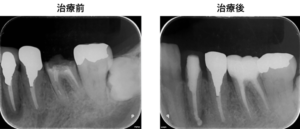

治療後

左下6の歯は器具の破折があり他院では治療不可と言われたそうですが、マイクロスコープ下での根管治療にて器具を除去して根管治療を完遂しました。また、炎症によるやや大きな骨吸収がみられた左下4番の歯も保存でき、治癒に導くことができます。治療困難であった歯を保存できて、患者様はとても喜ばれておられました。